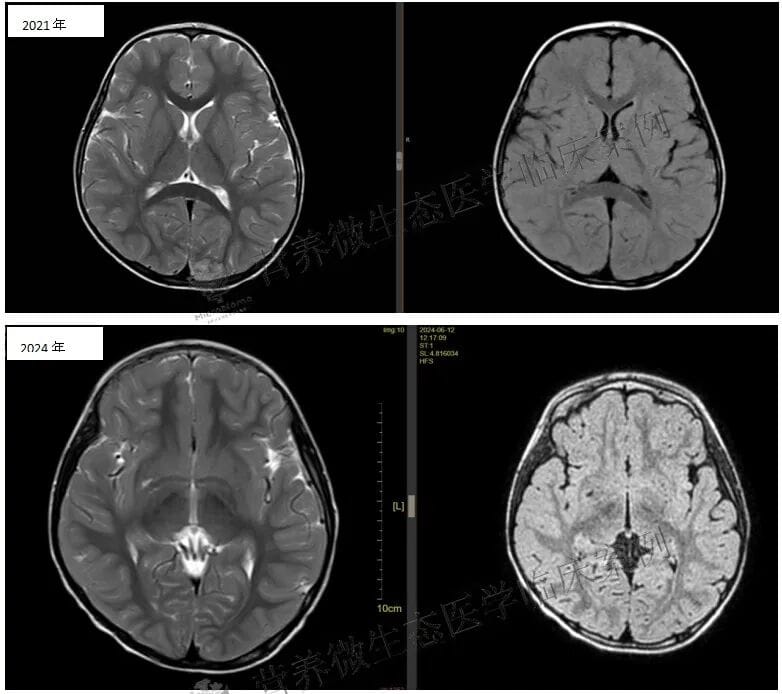

在启动BF839治疗(每日两次,每次一包)后,患儿于首次丙球输注后3个月再次接受了第二次丙种球蛋白治疗,至此共完成两次免疫调节。目前的联合治疗方案(吡仑帕奈、BF839及阶段性丙球)取得了阶段性成效:患儿至今已无临床发作,认知、语言和运动功能较前改善,脑电图放电指数也有所下降。

然而,本案例的诊治难点依然存在:异常脑电放电仍未完全消除,且GRIN2A突变所致的发育落后已是既定事实。下一步的治疗考虑包括调整抗癫痫发作药物,例如尝试换用布立西坦,或探讨每月进行一次免疫抑制剂治疗的可能性,以期进一步控制电生理异常,促进神经功能的最大限度恢复。